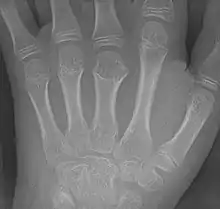

Brachymetacarpia or brachymetacarpalia is a medical condition in which the metacarpal bones of the hands are shortened.[1] The equivalent condition in the foot is brachymetatarsia, in which the metatarsal bones are shortened. Brachymetacarpia is typically congenital and presents in childhood or early adolescence, but it can also be associated with other acquired syndromes or endocrinological conditions. While cosmetic appearance is the most common concern of affected individuals, brachymetacarpia may also affect hand function due to alterations in muscle and tendon length. Treatment usually involves lengthening of the affected bone(s), either acutely with a bone graft or gradually with an external fixator.[2]

This condition is one of the causes of brachydactyly.